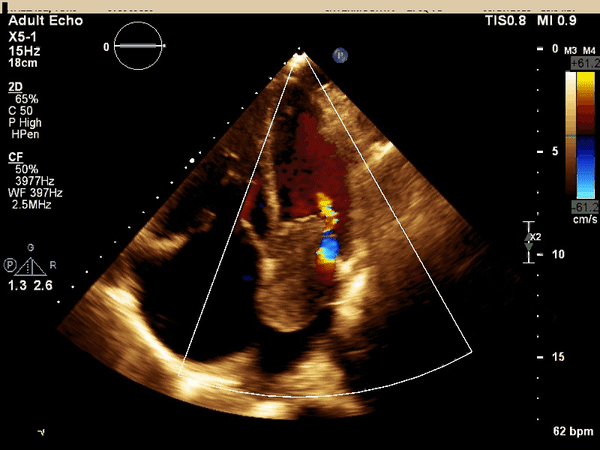

The above echo images demonstrate several abnormalities.

There is a large left atrial mass measuring 5.5 x 3 cm,

The mass is obstructing mitral inflow and causing moderate mitral regurgitation,

There is severe tricuspid regurgitation and right atrial dilation

confirmed by the absence of coaption of the tricuspid leaflets and

systolic flow reversal in the inferior vena cava.